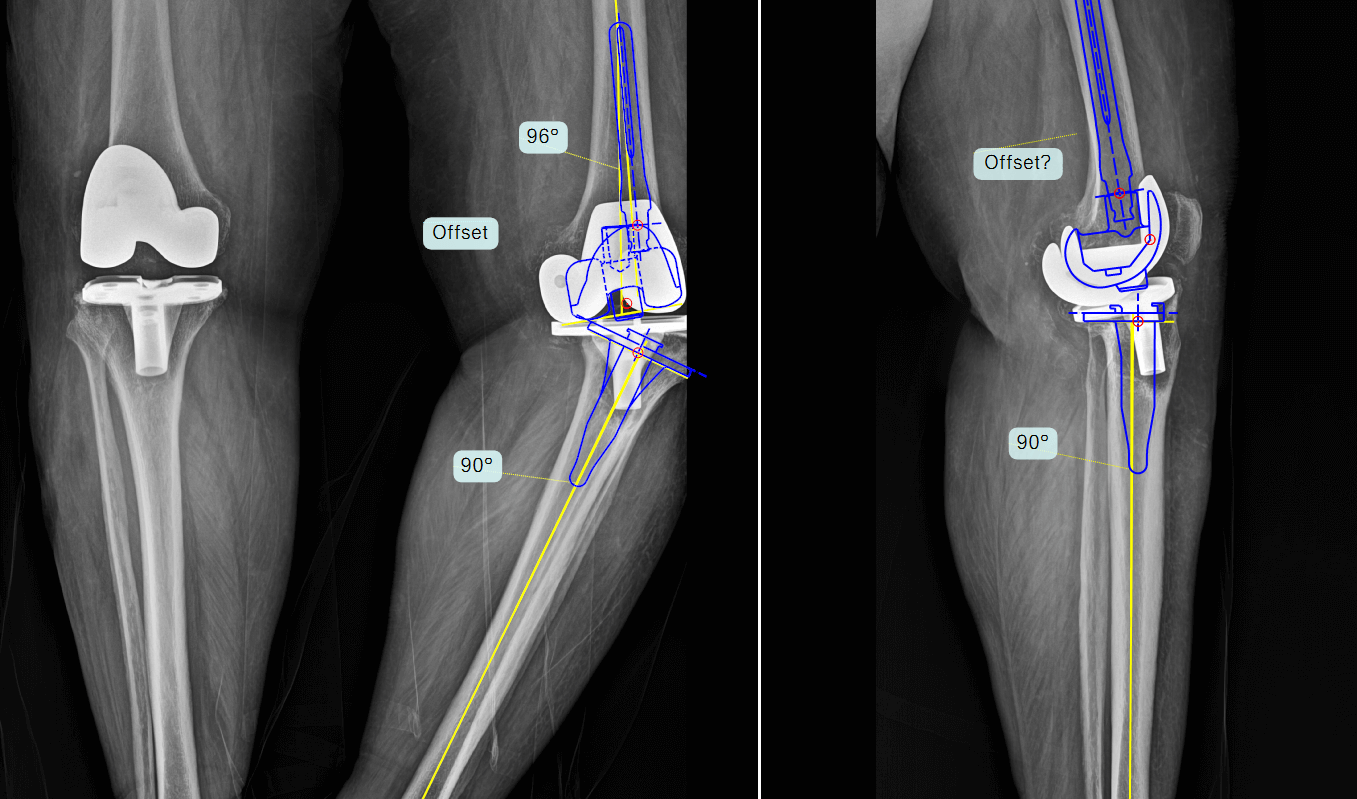

Dr. Greenberg and his team used TraumaCad orthopedic planning software to plan the patient’s knee revision surgery. Dr. Greenberg explains that “TraumaCad is particularly useful in revisions, as it helped us to anticipate challenges, such as areas of bone loss and the need for special implants. We used the patient’s right knee, whose size we knew from her operative report, to set the calibration to 127%, to allow us to plan components matching the patient’s anatomy.”

Opting for a patient-specific strategy, Dr. Greenberg and his surgical team selected a hinged knee implant that is specifically designed for immediate post-surgery stability and weight-bearing. The TraumaCad preoperative planning process revealed that the patient required a smaller-than-average implant. By using preoperative planning software, the team was aware of this need and able to procure the implant in advance, helping to avoid any delays or complications due to non-availability of the correct implant during surgery.